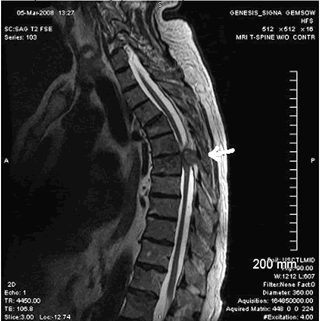

Магнитно-взвешенное изображение (MPT).

T1-взвешенное изображение:

- Непрерывный оссификат расположенный кзади от тел позвонка, распространяющийся на сагиттальных изображениях на несколько уровней.

Т2-взвешенное изображение.

- Картина ОЗПС схожа с картиной на Т1.

- Визуализация спинного мозга с наличием гиперинтенсивного сигнала коррелируется с миеломаляцией и отеком.

Сужение позвоночного канала со сдавлением спинного мозга на МРТ грудного отдела позвоночника опухолью.

МРТ позвоночника. Сагиттальная Т2-взвешенная МРТ шейного отдела позвоночника. Стеноз позвоночного канала обызвествленной задней продольной связкой.